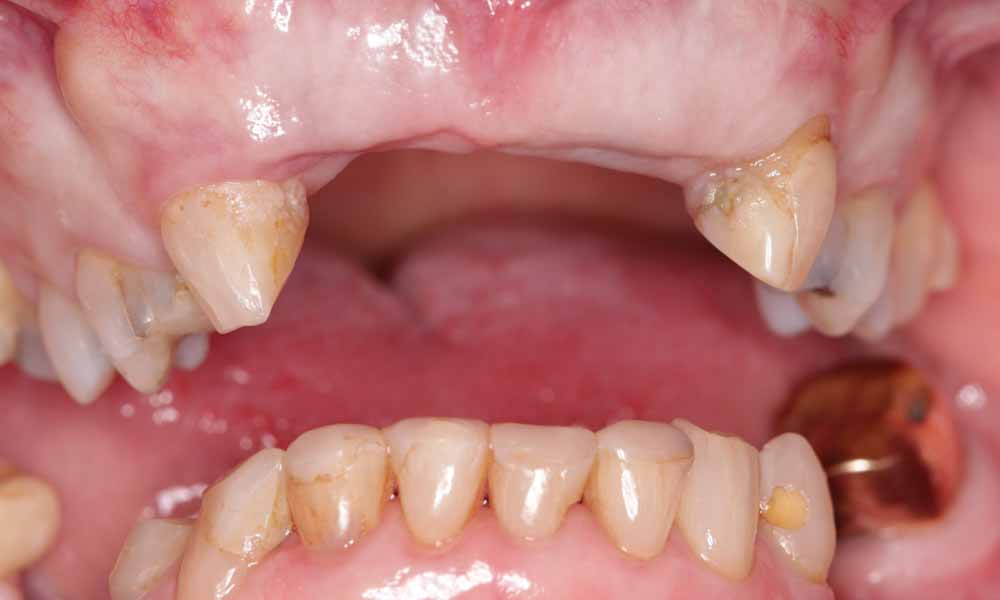

Case Study 2

Missing upper front teeth

Gap restored with 4 unit implant bridge